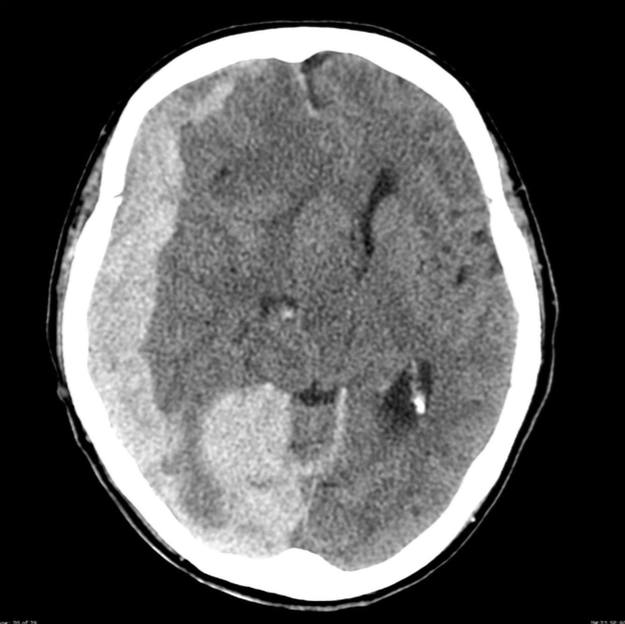

腦實質出血 (Intraparenchymal hemorrhage)

image